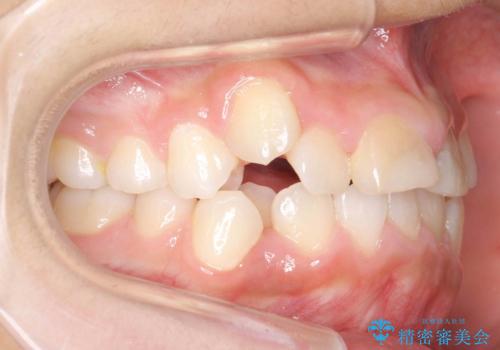

- 前歯のガタガタを主訴に来院。

神経の治療を先に行い、ワイヤー矯正を行いました。

上下の小臼歯を抜歯しています。